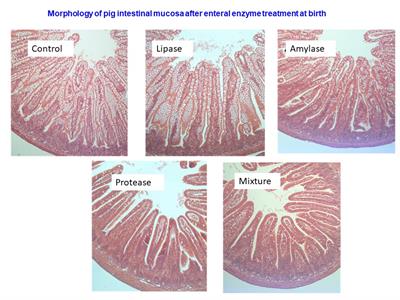

Phospholipids and Sphingolipids in Nutrition, Metabolism, and Health